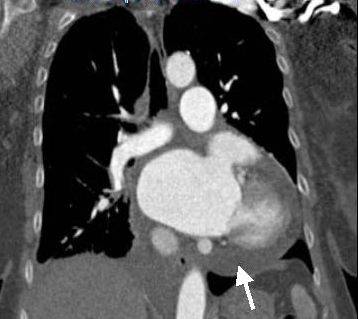

Следующей стадией перикардита является накопление жидкости в полости перикарда с развитием экссудативного перикардита (Рис. 1, б, в). При медленном накоплении жидкости существенных гемодинамических сдвигов может не быть, в то время как быстрое накопление экссудата при определенных состояниях быстро приводит к развитию тампонады сердца. Тампонада сердца — сдавление сердца экссудатом, является грозным осложнением, угрожающим жизни пациента.

Тампонада сердца. Стрелкой показана жидкость в полости перикарда

При этом за счет уменьшения наполнения правых отделов сердца формируется застой крови в большом круге кровообращения с увеличением печени, появления отеков нижних конечностей и жидкости в брюшной полости. Из-за уменьшения объема крови, который выбрасывается из левого желудочка, нарушается питание всех органов и тканей, особенно клеток головного мозга. Тампонаду сердца, как осложнение перикардита, можно заподозрить при повышении венозного давления (выбухание яремных вен, появление жидкости в брюшной полости, боли в правом подреберье за счет увеличения печени) на фоне падения артериального, появления сердцебиения, одышки при отсутствии хрипов в легких.